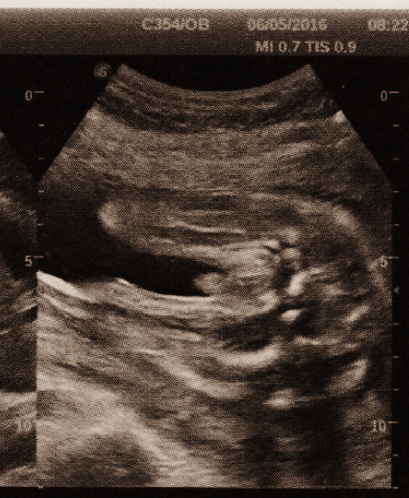

Так девочка или нет?🙈Фото узи

Результаты: УЗИ, КТГ, доплера, скринингаХодили мы с мужем на узи в 16 полных недель именно чтоб узнать пол.

Узистка сначала начала говорить «видите,тут ровная площадочка» (хотя в это время нифига не видела 😂 я радостно кивала головой,понимая к чему она это ведёт».

Потом стала спрашивать кто у нас первый.Сказали что мальчик,который заказал себе братика,потому что для девочки придётся покупать новые игрушки девчачьи 😅.

На что она сказала «игрушка все же похоже придётся покупать»)).

Потом цитирую «девочка.но 1% оставлю на то что это может быть мальчик.»

Потом неувереннее начала говорить чтоб мы пока не расстраивали сына,рассказывая ему про сестричку,а то вдруг потом окажется что все же братик 🤨 И спросила у меня про «принимаете ли вы гормоны или бреете ноги?»

Не принимаю,но ноги брею 🙈😂 на что сказала «есть малюсенький бугорок или это гипертрофированный клитор или такой маленький писюн».Что ещё больше заставляет сомневаться в этих 99 обещанных процентах))

К слову с сыном тоже ходила на узи в 16 недель и там узист кричал «мальчик!тут такое хозяйство !!!» 😂 что сомнений не было))

Вобще изначально я настраивалась на мальчика,но как и любой другой маме хочется девчушку.Муж тоже хочет девочку.Может я просто осознать не могу,поверить что так бывает 🙈 как по заказу))

Вобще уже записалась 18го числа на 2й скрининг.Будет 20 недель,там конечно все и скажут думаю окончательно.Надеюсь))

Вот на таком же сроке мой сын.

на кого похоже?